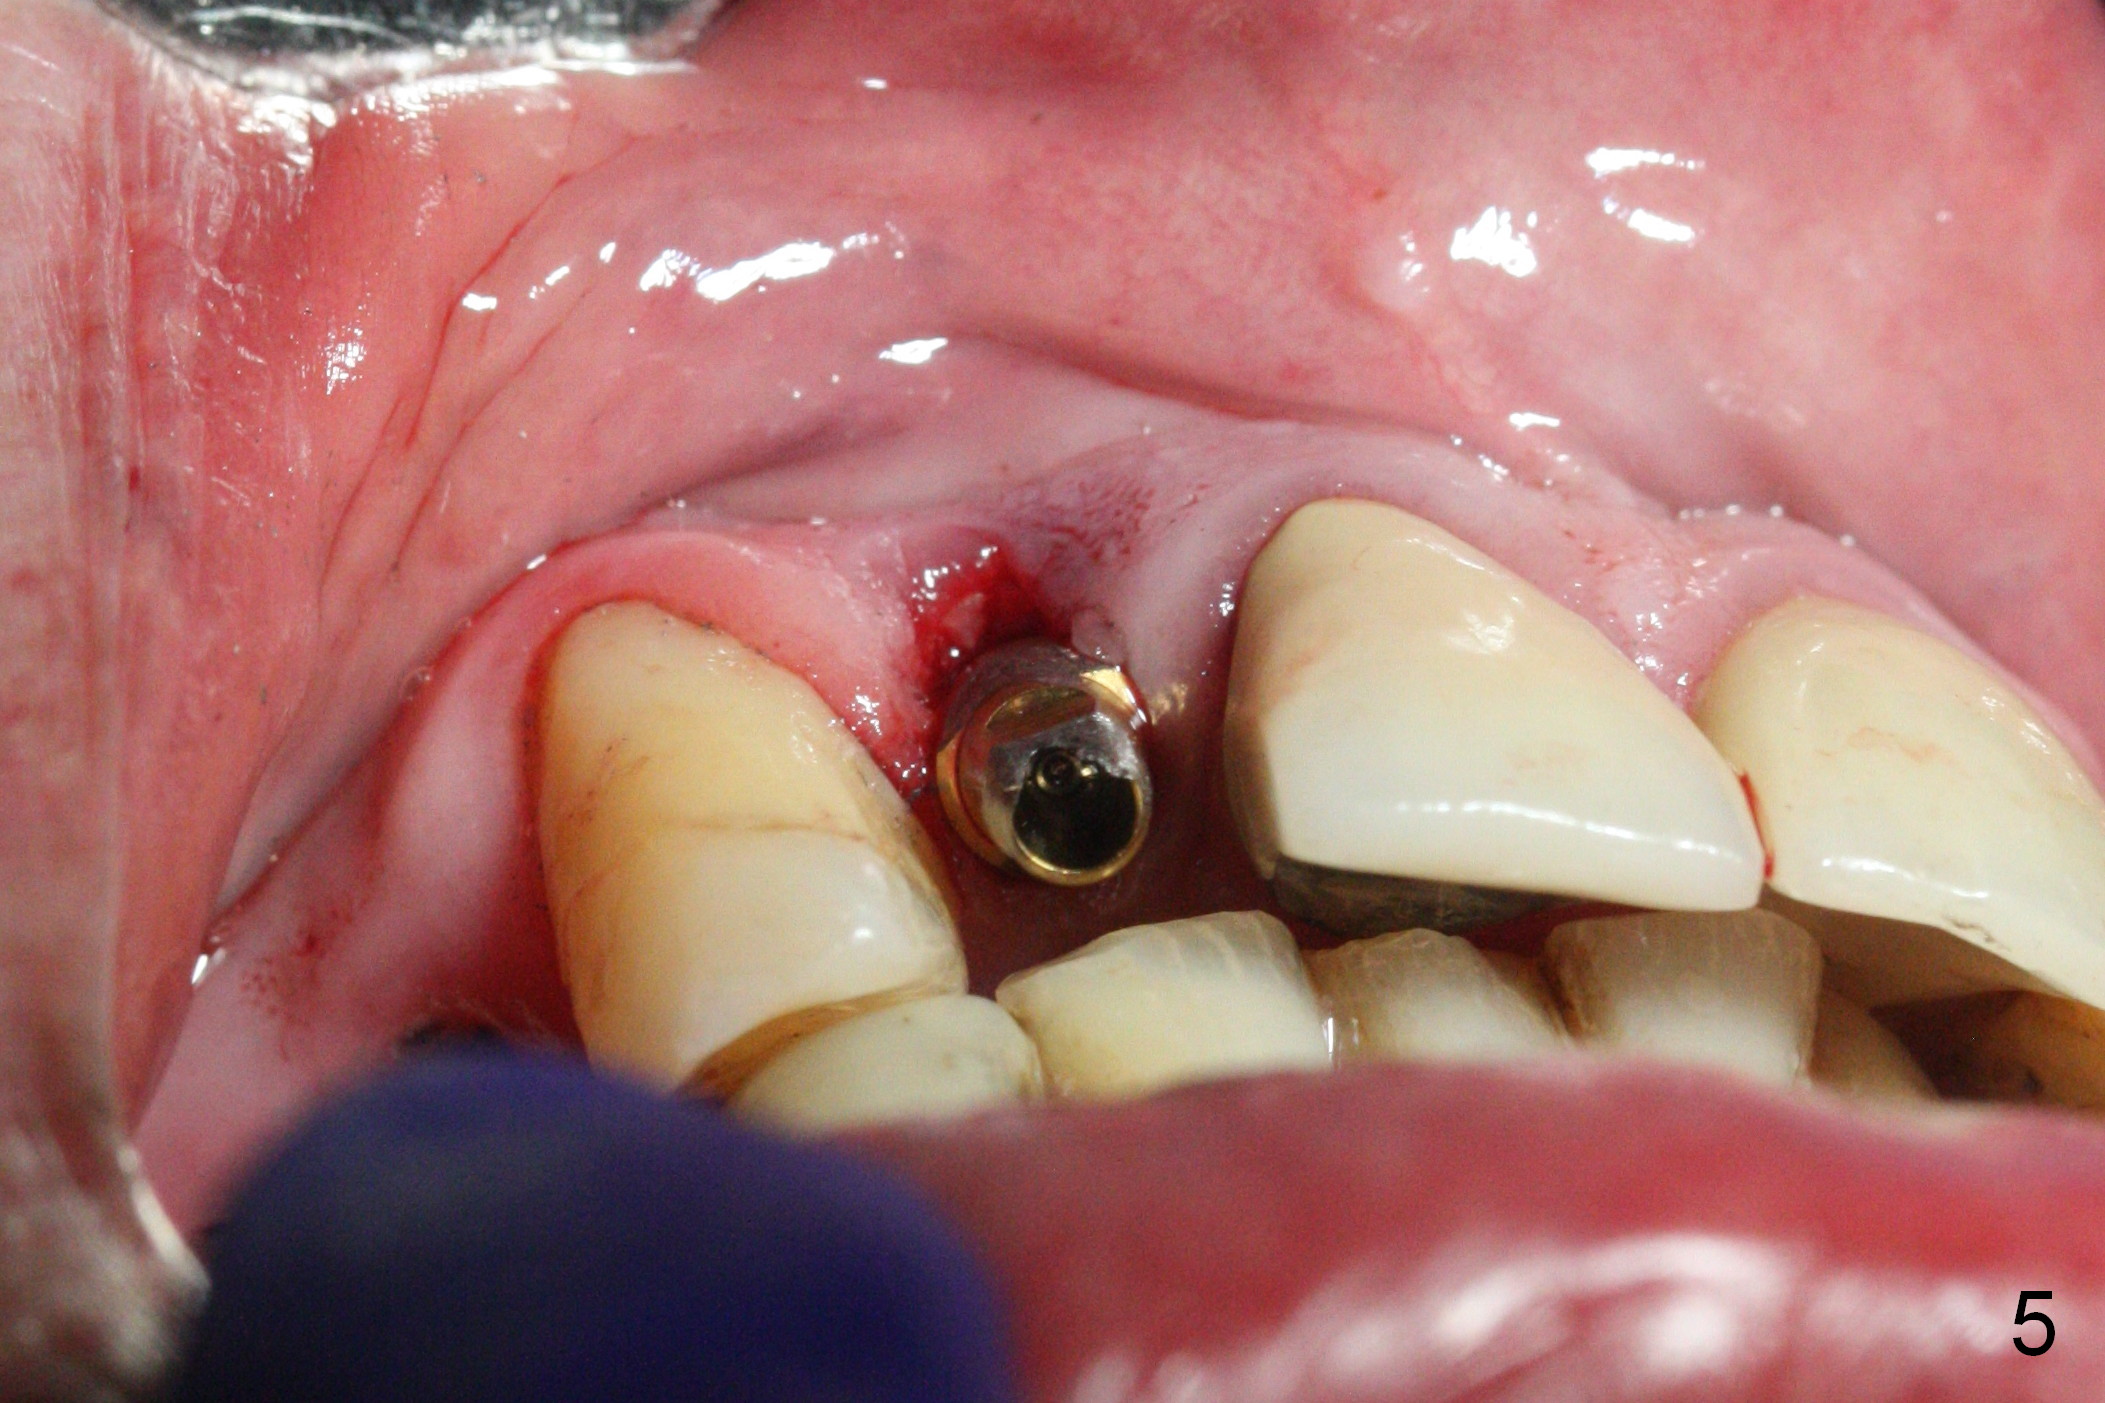

The residual root at #7 is fairly well exposed with buccal gingival recession (Fig.1). The implant placement is flapless (Fig.2-7). What is not shown is that the 3.8x13 mm implant is buccally subcrestally placed (Fig.3). After 1st round of bone graft buccal to the implant, a 4.5x5(5) mm abutment is immediately placed and prepared (Fig.4,5). An immediate provisional is placed after 2nd round of bone graft subgingivally buccally (Fig.6,7). Note the bulging gingiva (*), as compared to that in Fig.4,5. The long implant is chosen because of anterior deep bite (Fig.4) and lack of posterior support (Fig.7).

The gingiva adapts well to the provisional 1 week postop (Fig.8). The buccal gingiva remains recessive and the buccal plate is concave 5.5 months postop (Fig.9-11). It appears that the coronal portion of the buccal plate is resorbed 12 months postop (6 months post cementation, Fig.12 >). Socket shield or smaller diameter implant should have been done to avoid bone loss. Reanalysis of CBCT reveals that implantation apparently increases the bone width and that the buccal plate resorption is not so severe (Fig.13,14 (>: coronal end of the buccal plate)). Panoramic X-ray is taken 2 year 5 month post cementation.